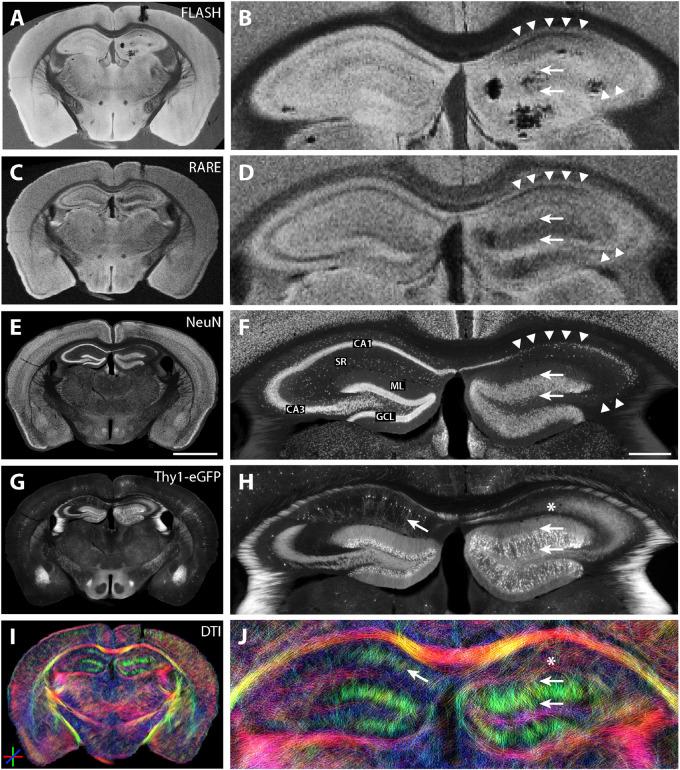

Mesial temporal lobe epilepsy (MTLE) is the most common type of focal epilepsy. It is frequently associated with abnormal MRI findings, which are caused by underlying cellular, structural, and chemical changes at the micro-scale. In the current study, it is investigated to which extent these alterations correspond to imaging features detected by high resolution magnetic resonance imaging in the intrahippocampal kainate mouse model of MTLE. Fixed hippocampal and whole-brain sections of mouse brain tissue from nine animals under physiological and chronically epileptic conditions were examined using structural and diffusion-weighted MRI. Microstructural details were investigated based on a direct comparison with immunohistochemical analyses of the same specimen. Within the hippocampal formation, diffusion streamlines could be visualized corresponding to dendrites of CA1 pyramidal cells and granule cells, as well as mossy fibers and Schaffer collaterals. Statistically significant changes in diffusivities, fractional anisotropy, and diffusion orientations could be detected in tissue samples from chronically epileptic animals compared to healthy controls, corresponding to microstructural alterations (degeneration of pyramidal cells, dispersion of the granule cell layer, and sprouting of mossy fibers). The diffusion parameters were significantly correlated with histologically determined cell densities. These findings demonstrate that high-resolution diffusion-weighted MRI can resolve subtle microstructural changes in epileptic hippocampal tissue corresponding to histopathological features in MTLE.

内侧颞叶癫痫(MTLE)是最常见的局灶性癫痫类型。它常与MRI异常表现相关,这些异常是由微观层面潜在的细胞、结构和化学变化引起的。在本研究中,探究了在MTLE的海马内红藻氨酸小鼠模型中,这些改变在多大程度上与高分辨率磁共振成像检测到的影像特征相对应。使用结构和扩散加权MRI对9只处于生理状态和慢性癫痫状态的动物的小鼠脑组织固定海马和全脑切片进行了检查。基于与同一样本免疫组织化学分析的直接比较,对微观结构细节进行了研究。在海马结构内,可以看到与CA1锥体细胞和颗粒细胞的树突、苔藓纤维和谢弗侧支相对应的扩散流线。与健康对照相比,在慢性癫痫动物的组织样本中可检测到扩散率、分数各向异性和扩散方向的统计学显著变化,这与微观结构改变(锥体细胞变性、颗粒细胞层分散和苔藓纤维发芽)相对应。扩散参数与组织学确定的细胞密度显著相关。这些发现表明,高分辨率扩散加权MRI能够分辨癫痫海马组织中与MTLE组织病理学特征相对应的细微微观结构变化。